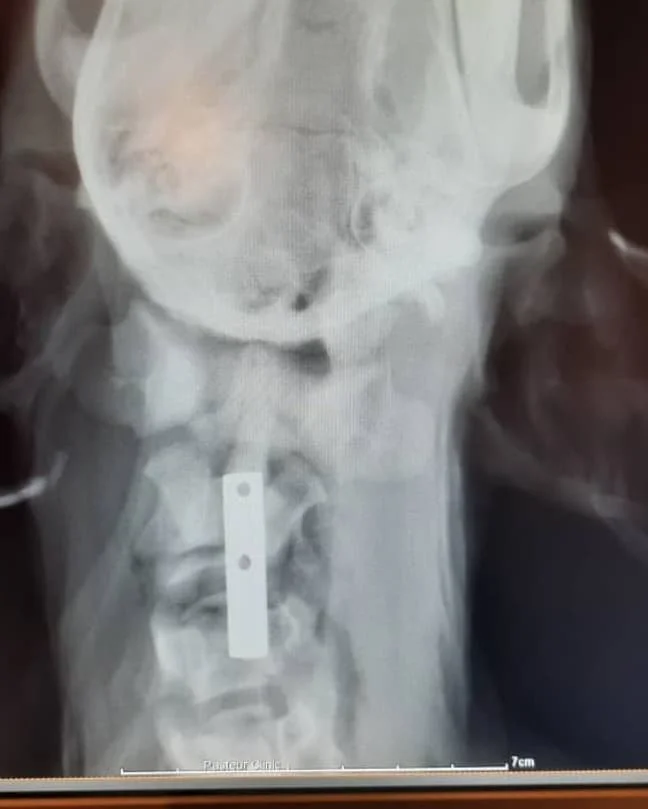

At the clinic, his condition was critical. The cervical vertebrae in his neck were fractured, leaving him in excruciating pain. Many debated euthanasia, fearing that survival was impossible and that keeping him alive would only prolong his suffering.

But the team chose hope. A skilled surgeon undertook an hours-long operation, carefully stabilizing his spine with plates and precision. It was a race against time, and against despair.